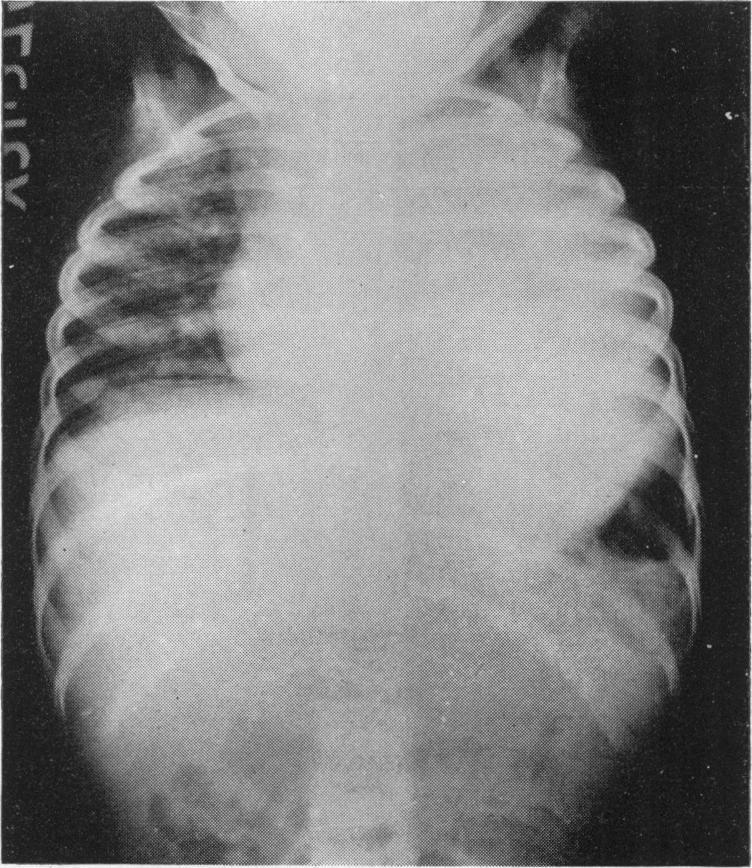

Arch Dis Child. 1961 Oct;36(189):530-6. doi: 10.1136/adc.36.189.530.